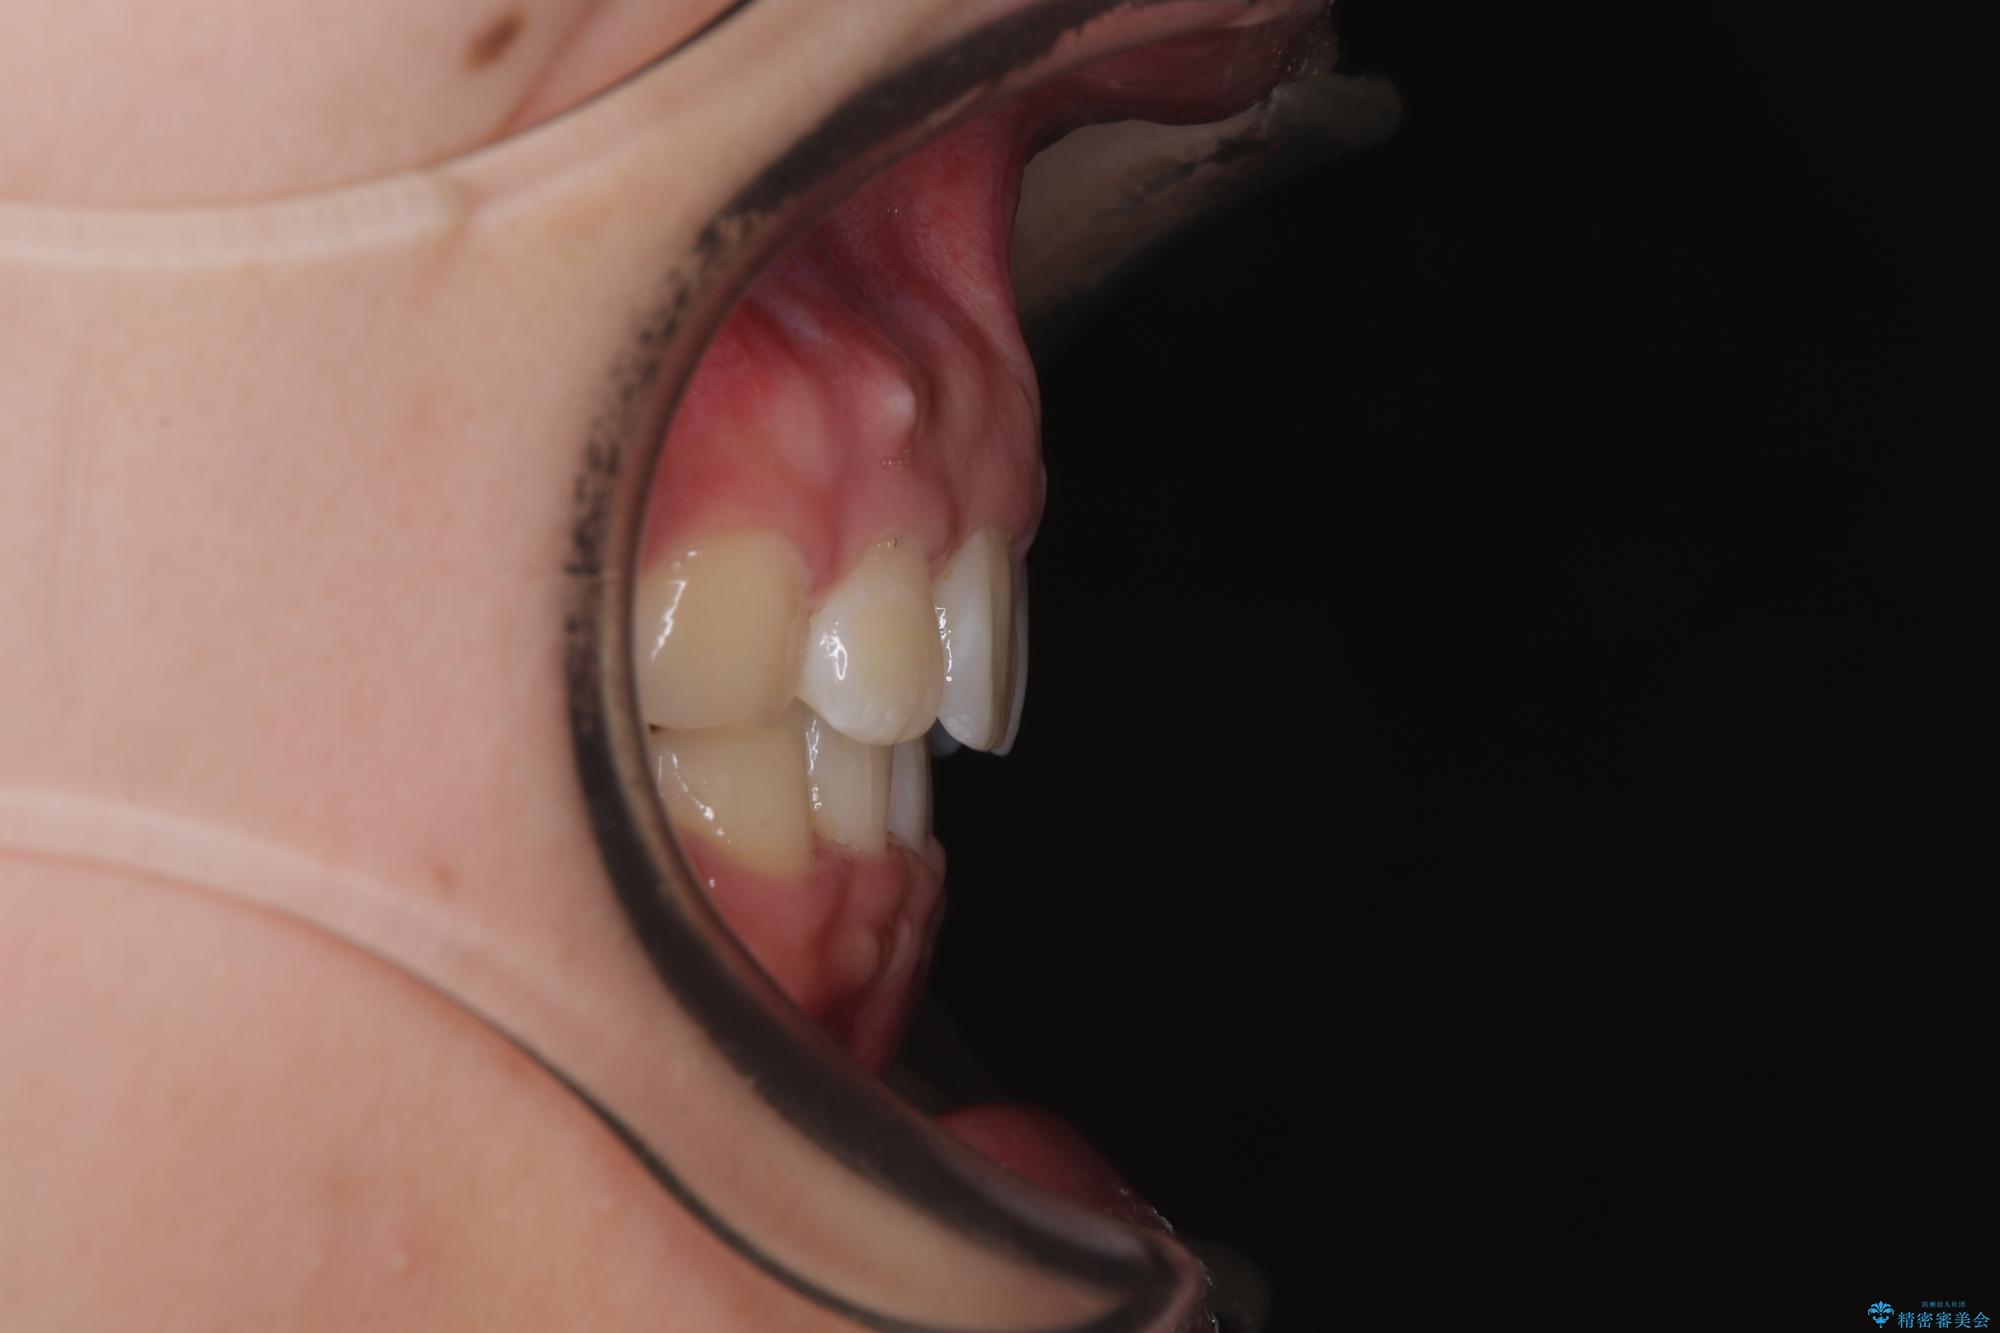

- 上顎前歯が飛び出していて唇がうまく閉じられないとのことで来院された患者様です。

くちばしのように前歯が突出していたため、口元を積極的に引っ込めるために、上下左右の小臼歯4本を抜歯することとしました。